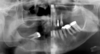

explain the steps in which this periapical periodontitis shown has occured

1) bacterial ingress via caries/ cracks . fractures / marginal gaps in restorations 2) reversible pulpitis ---> irriversible pulpitis ---> pulp necrosis ---> root canal system becomes infected 3) inflamm response happens 'periapical periodontitis' occurs to confine infection/ bacterial ingress 4) the body results in resorption, formation of granulation tissue (cysts may also occur) resulting in radiolucency 5) bone foramtion may also occur - may result in corticated (white) margin and/or general sclerosis of adjacent bone (to wall off infection)